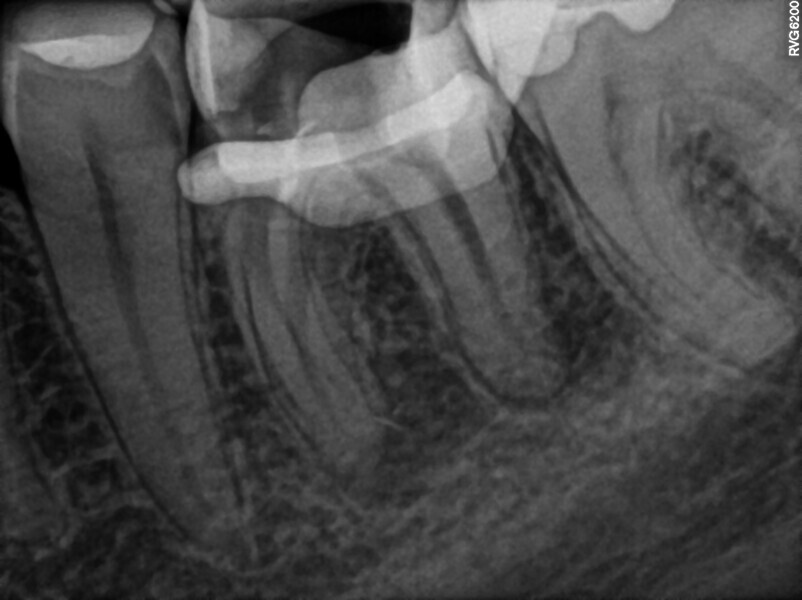

Fig. 2: Pre-op CBCT scan. Broken file far beyond the canal curvature.

Fig. 3: Pre-op CBCT scan. Tip of the broken file located below the junction of the mesiobuccal and mesiolingual canals.

The periapical radiograph and the CBCT scan revealed that the file had broken far beyond the curvature in the mesiobuccal canal and below the junction with the mesiolingual canal. Also, a periapical lesion was visible around the apices of the mesial and distal roots (Figs. 1–3). The length of the file was approximately 5 mm. Bypassing the file through the mesiolingual canal would have been a risky procedure because it may have caused the fracture of the second instrument and the obturation may also have been very challenging. Thanks to SWEEPS technology and a bioceramic sealer, an alternative approach could be taken. After administering anaesthesia and placing a dental dam, the temporary restoration was removed (Figs. 4 & 5). The pulp chamber was rinsed with 5.25% sodium hypochlorite and the irrigant activated with ultrasonics. After cleaning the chamber of the tooth, the dental dam and clamp were rinsed with water and dried and flowable dental dam was placed to seal the tooth and enlarge the space in the pulp chamber for the laser-activated irrigation (Fig. 6). Activation was performed with the SkyPulse laser (Fotona). The AutoSWEEPS mode was chosen. The power of activation was set to 1 W. The flat SWEEPS 300/20 fibre tip was used (Fig. 7). The tip was placed slightly below the orifice of the mesiobuccal canal for the majority of the irrigation with sodium hypochlorite. After 120 seconds of activation with sodium hypochlorite, the tip was placed in the pulp chamber to activate the sodium hypochlorite in all the canals simultaneously for 30 seconds. This procedure was continued for 30 minutes. Only the distal canal was shaped with rotary files, up to size 40/.04. Both mesial canals remained the same size as they were before the file broke during the primary treatment. Finally, the canals were flushed with EDTA activated with AutoSWEEPS at a power of 0.4 W, and sodium hypochlorite was activated for three cycles with AutoSWEEPS at a power of 0.6 W and with a 30-second break for the resting phase. The irrigant flow between the mesiobuccal and mesiolingual canals was rapid, indicating that obturation could be performed.